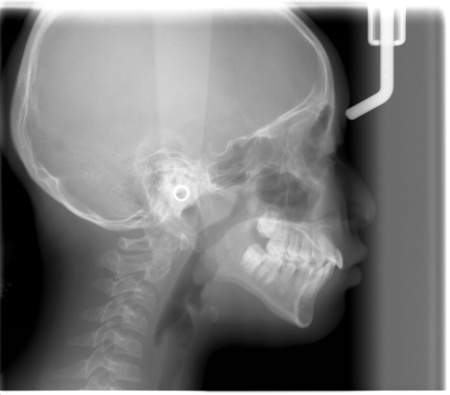

| カウンセリング | 拝見したところ、上下の前歯がずれたりねじれたりして、デコボコの歯並びになっています。お顔の骨格を確認すると、上下ともに歯並びのアーチの幅が狭くなっており、将来的に永久歯が正しい位置に並ばないおそれがありました。 さらに、下あごと比較して上あごが小さく、やや受け口の傾向も見られます。 患者様は口をポカンと空けて口呼吸をする癖があり、それが原因で舌の位置が通常より下がって歯並びの乱れが助長されている可能性があります。 この状態を放置すると、見た目の問題だけでなく、口呼吸によって口の中が乾燥し虫歯になりやすくなることや、睡眠がしっかりとれず成長に悪影響を及ぼすリスクがあるため、矯正治療が必要と診断しました。 |

診断結果を踏まえて、永久歯が全て生え揃ってから歯並びを整える「成人矯正」があることをお伝えしたところ、親御様はできれば今のうちに改善したいとご希望だったため、「顎顔面矯正治療」を提案し同意いただきました。

顎顔面矯正治療は、あごの成長を利用しながら今後生えてくる永久歯がきれいに並ぶように促す方法で、当院では、上の歯並びが狭く、呼吸や睡眠に問題を起こしている場合にこの方法を提案しています。 まず、上下の歯並びの幅を広げるための装置として、上あごには「急速拡大装置」、下あごには「リンガルアーチ」を装着します。 その後、歯並びの幅が十分に広がった時点で上の前歯はきれいに並びましたが、下の前歯にはまだデコボコが残っていたため、ワイヤー矯正の「マルチブラケット装置」を装着して部分矯正を行いました。 |